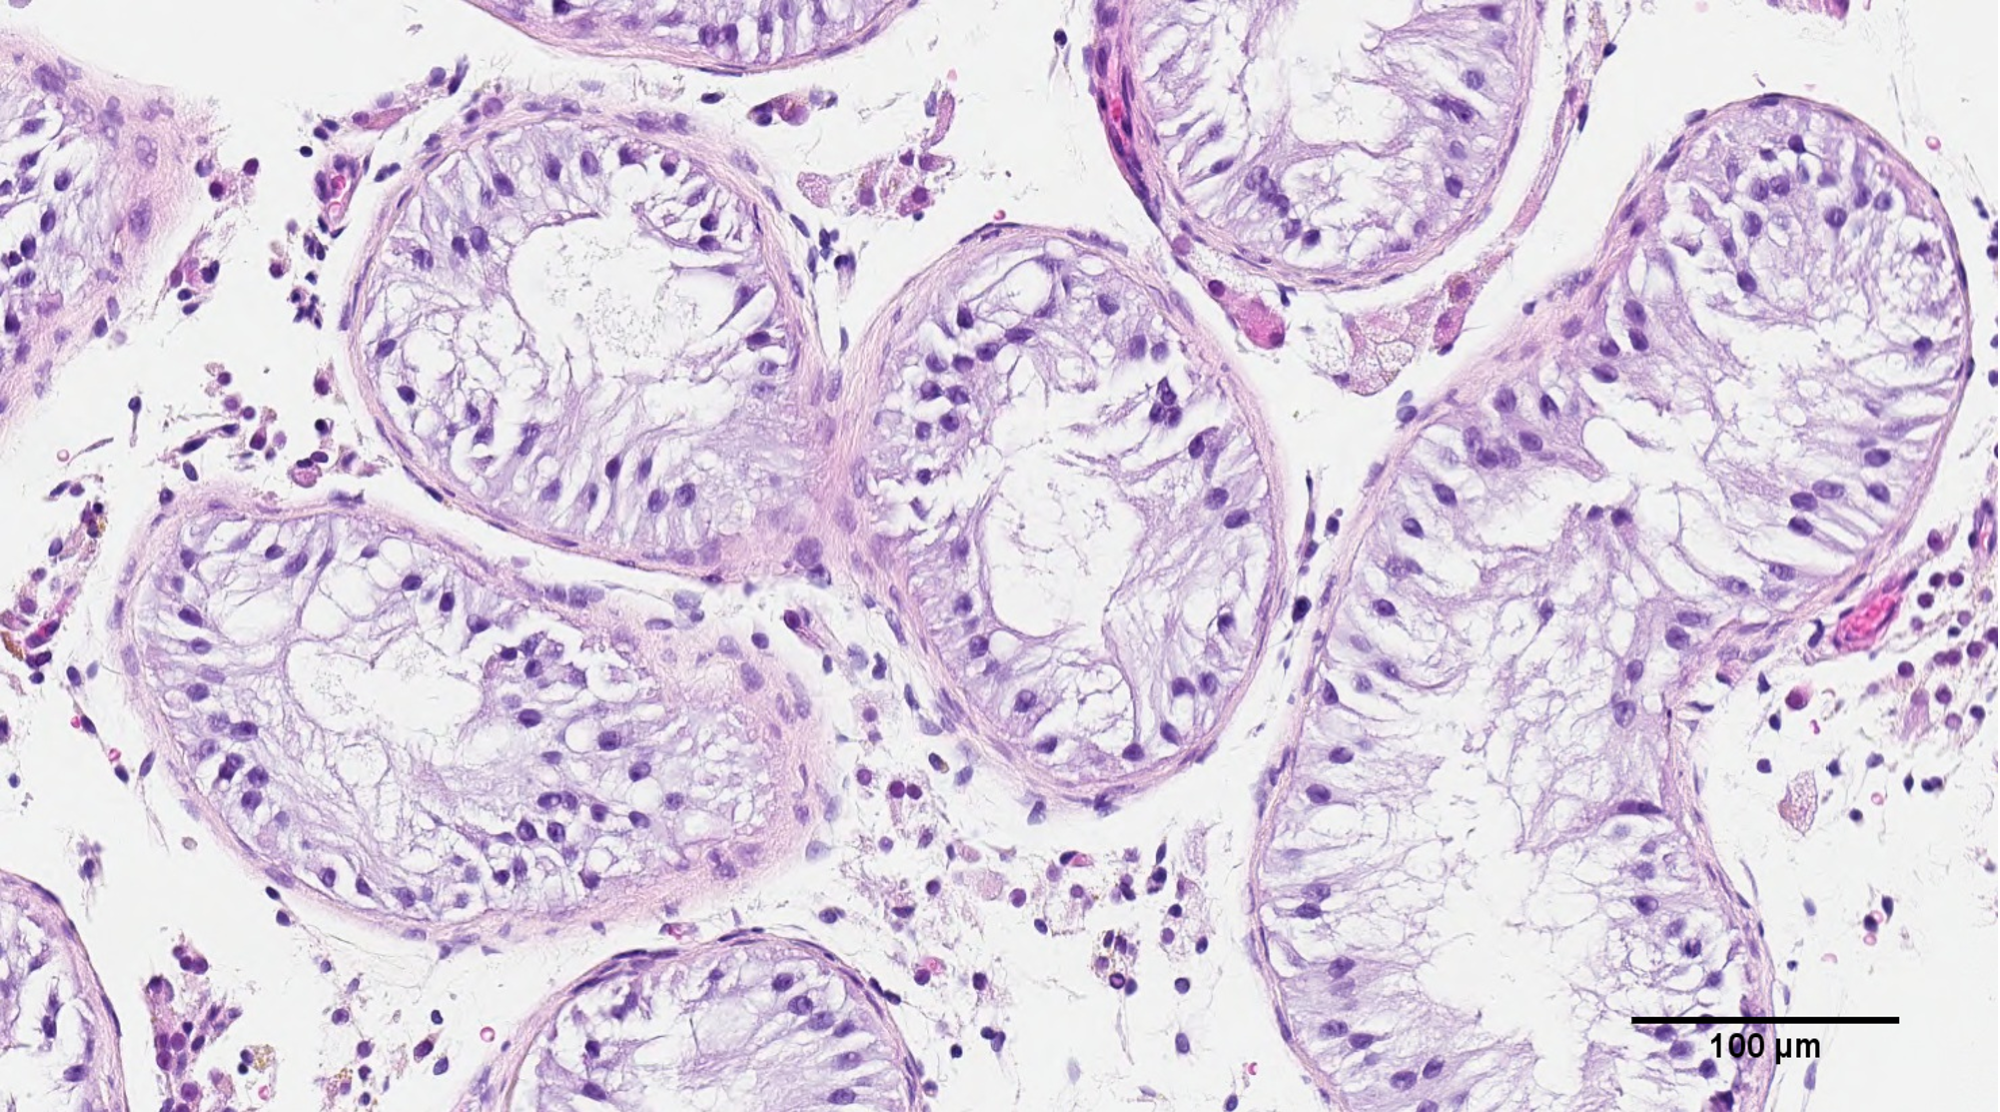

Our research is based on the understanding that normal sperm production is a highly complex and coordinated event among roughly 20 cell types within the testicle that require multi-directional cell communication through sending molecules between them or being in physical contact with each other. These interactions are specifically coordinated in the seminiferous tubule within the human testis.

Biopsy of Testicular Cells

Image Credit: The University of British Columbia